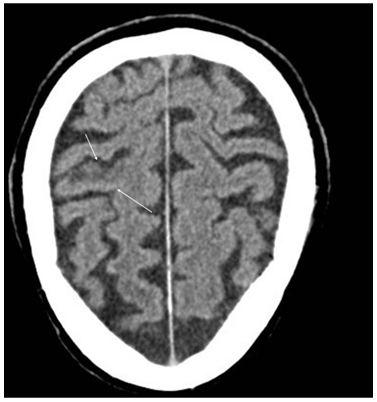

A 71-year-old man was admitted to the hospital with acute myocardial infarction which resulted in significant cardiac dysfunction. He also developed atrial fibrillation during this period, for which he was anticoagulated with warfarin. During the period of recovery (7 days after admission), he suffered a right hemispherical stroke with associated left hemiparesis (Figure 1).

Figure 1: CT scan showing cortical and subcortical low-density in the right pre-central gyrus (arrows)

2. The EEG shows a differential reduction in sleep spindles on the right sided EEG leads (C4-A1) compared to the left sided EEG (C3-A2) (see arrows in Figure 3 below). The CT scan of the head did not show any evidence of thalamic involvement, with the right sided stroke. A reduction in sleep spindles on the ipsilateral side of hemispherical cortical stroke has been reported and this has been thought to indicate that cerebral hemispheres play a major role in generation of synchronous sleep spindles.